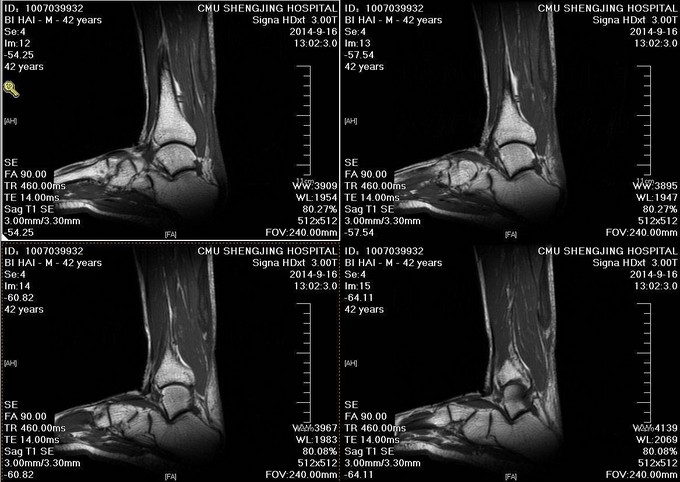

患者于2014年7月28日打排球时不慎摔伤,自觉左足跟部一过性剧烈疼痛,意识清醒。自觉足跟部及小腿后侧远端疼痛、行走时左足无力。于2014年9月10日就诊于当地医院,行相关查体后提示:左脚跟腱断裂。患者为进一步治疗门诊以“左跟腱断裂”为诊断收入病房

患者生命体征平稳,跟腱后方凹陷。局部可触及缺损,Thompson征阳性。

诊断:左陈旧性跟腱断裂 入院完善检查后,行左跟腱翻转修补术,术后踝关节跖屈石膏固定。